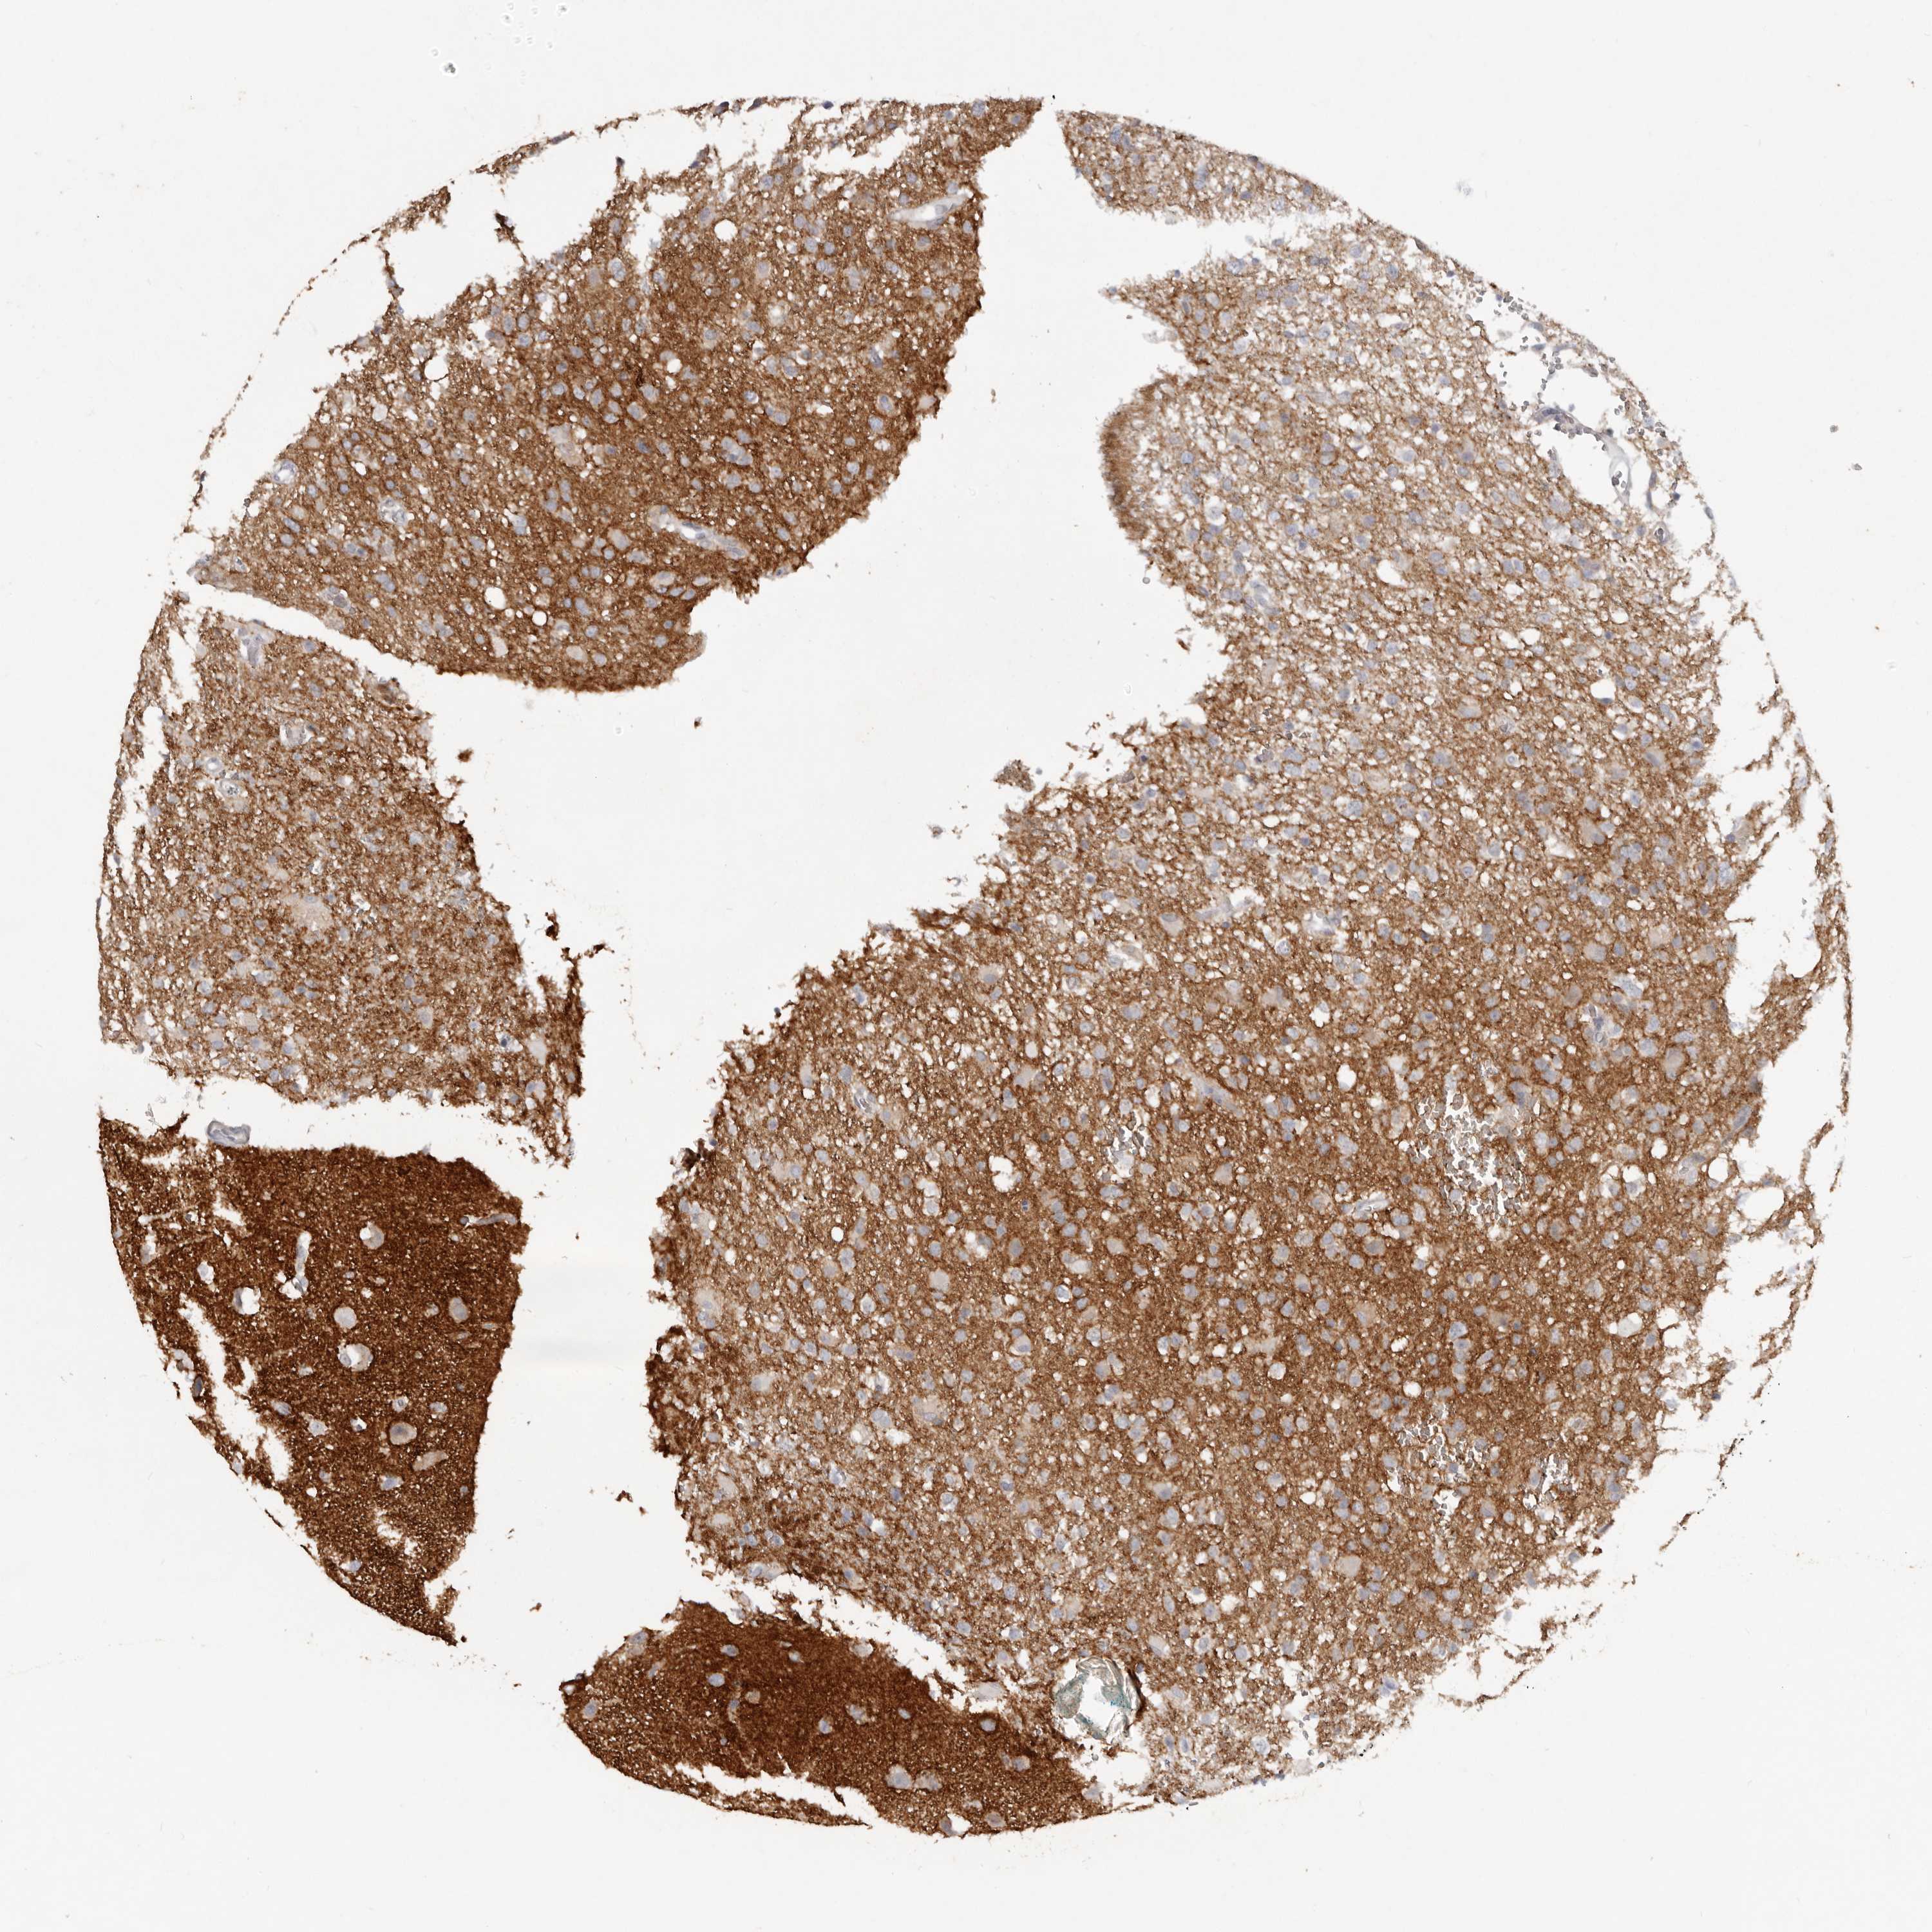

GLIOMA - Protein expressioni

A mouse-over function shows sample information and annotation data. Click on an image to view it in a full screen mode. Samples can be filtered based on level of antibody staining by selecting one or several of the following categories: high, medium, low and not detected. The assay and annotation is described here.

Note that samples used for immunohistochemistry by the Human Protein Atlas do not correspond to samples in the TCGA dataset.

Antibody stainingi

Antibody staining in the annotated cell types in the current human tissue is reported as not detected, low, medium, or high, based on conventional immunohistochemistry profiling in selected tissues. This score is based on the combination of the staining intensity and fraction of stained cells.

Each image is clickable and will lead to virtual microscopy that enables deeper exploration of all samples and also displays staining intensity scores, fraction scores and subcellular localization as well as patient and tissue information for each sample.

Antibody HPA027134

Antibody HPA027150

Antibody HPA029859

Antibody CAB022343

Staining

High

Medium

Low

Not detected

Intensity

Strong

Moderate

Weak

Negative

Quantity

>75%

75%-25%

<25%

None

Location

Nuclear

Cytoplasmic/membranous

Cytoplasmic/membranous,nuclear

Glioma, malignant, High grade

Glioma, malignant, Low grade

Glioblastoma, NOS